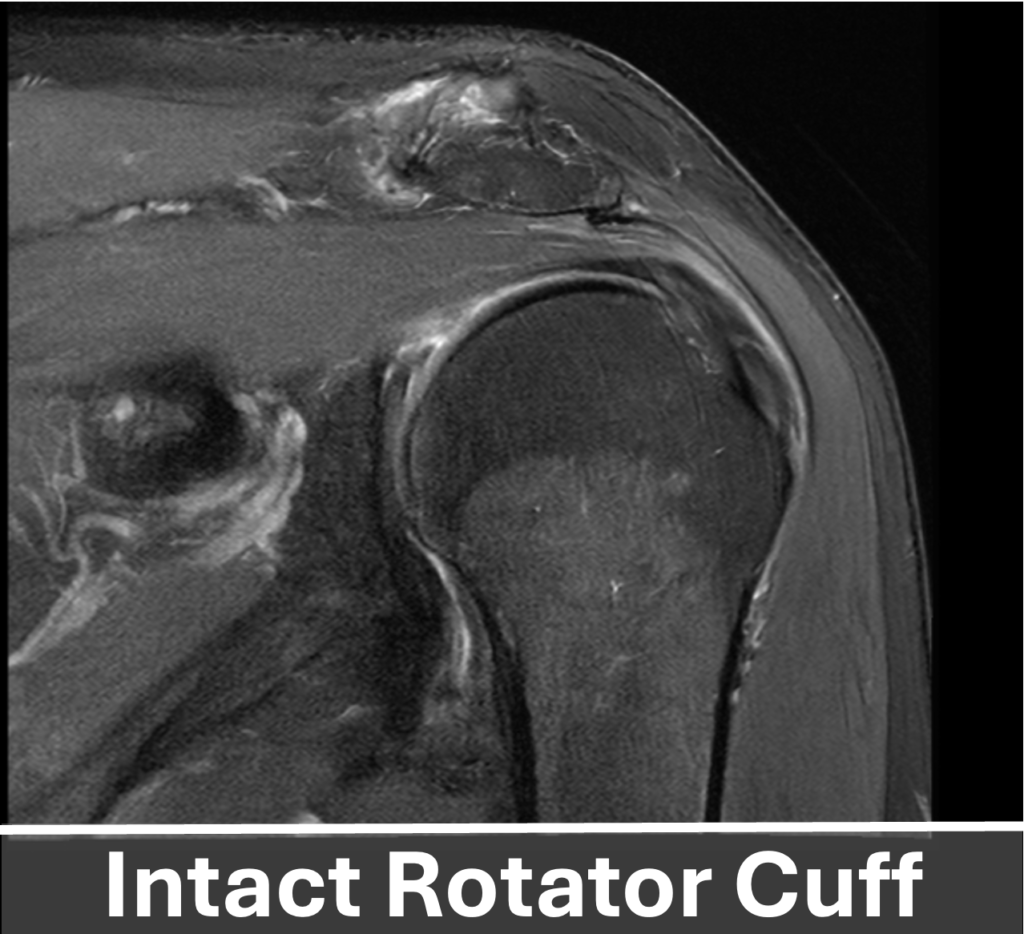

The rotator cuff is a group of four muscles that play a vital role in shoulder stability and movement. These muscles originate from the shoulder blade (scapula) with their tendons forming a “cuff” around the humeral head. Each muscle has a specific attachment on the humerus: the Subscapularis inserts on the front, the Supraspinatus inserts on the top, and the Infraspinatus and Teres minor both insert on the back of the shoulder. Together the rotator cuff allows you to lift, reach, and rotate your arm to perform everyday activities and sports.

A full-thickness rotator cuff tear occurs when a tendon is completely (100%) torn from the footprint. These tears are classified by size: small (< 1 cm), medium (1 – 3 cm), large (3 – 5 cm), and massive (> 5 cm). Acute full-thickness tears often result from a traumatic event typically causing immediate pain and loss of shoulder function. Timely surgical repair is generally recommended as delays can lead to tendon retraction and irreversible changes in the muscle. These changes include fatty infiltration and atrophy, a process where the healthy muscle will become irreversibly replaced with non-functional tissue, subsequently limiting the chances of a complete recovery.

Most rotator cuff tears gradually develop as an unfortunate consequence of our natural aging process. The rate of this process varies among individuals and can be influenced by genetics, occupation, and activity level. Chronic rotator cuff tears typically cause slowly worsening symptoms over time, including pain on the side of the shoulder, weakness with overhead activities or lifting, and, most notably, night pain that disrupts sleep.

Treatment of the rotator cuff depends on the severity of the tear. Partial-thickness tears involving < 50% of the tendon are usually debrided and may be augmented to promote healing. Tears > 50% thickness and full-thickness tears are repaired to the bone using suture anchors. The number of anchors (typically 1 to 5) depends on tear size, bone quality, and tendon condition. In cases of poor tissue quality, a graft may be used to support tendon healing and optimize recovery.